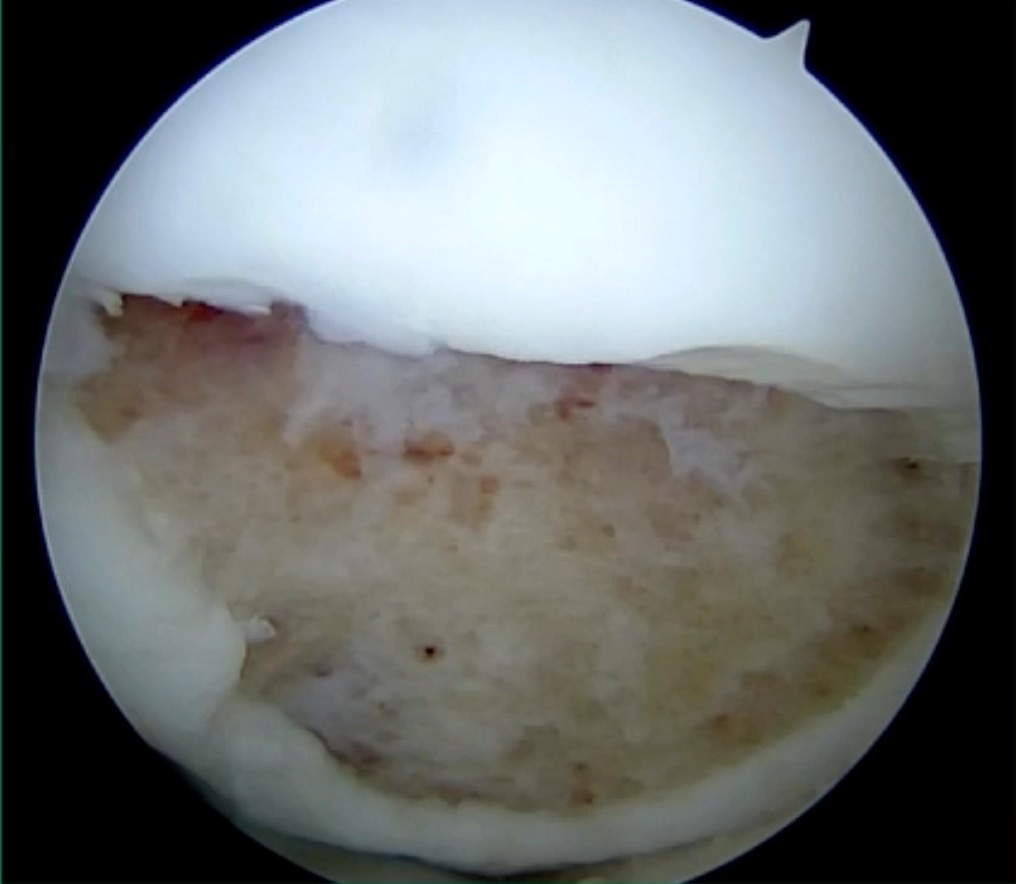

I thought I might be able to fix it. I had the conversation with the family, get in there, started taking it apart with a Vanguard elevator grasper. Behold, it’s really just cartilage fragments (Figure 2).

There’s two or three of them. We debrided it. It felt normal in six weeks, no complaints in three years. What are the results of juvenile debridement? They’re actually profoundly good. You would never expect this in the scheme of things, but the natural history of removing the piece is actually very good in the juvenile patient. However, once again, fix it if you can. Debride it, if you can’t. If they get symptoms, we restore it, and then never leave unstable fragments.